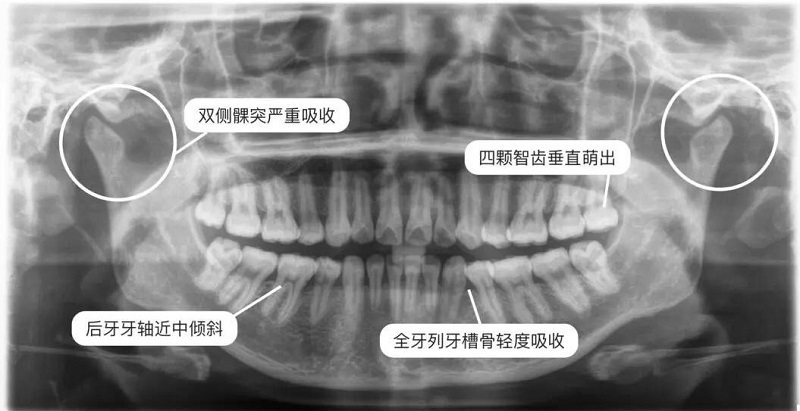

全景片(曲面斷層片)

曲面斷層在正畸方面應(yīng)用廣泛,優(yōu)點(diǎn)是:病人從治療開(kāi)始到完成期間牙齒發(fā)育和萌出過(guò)程可以很好的評(píng)估。